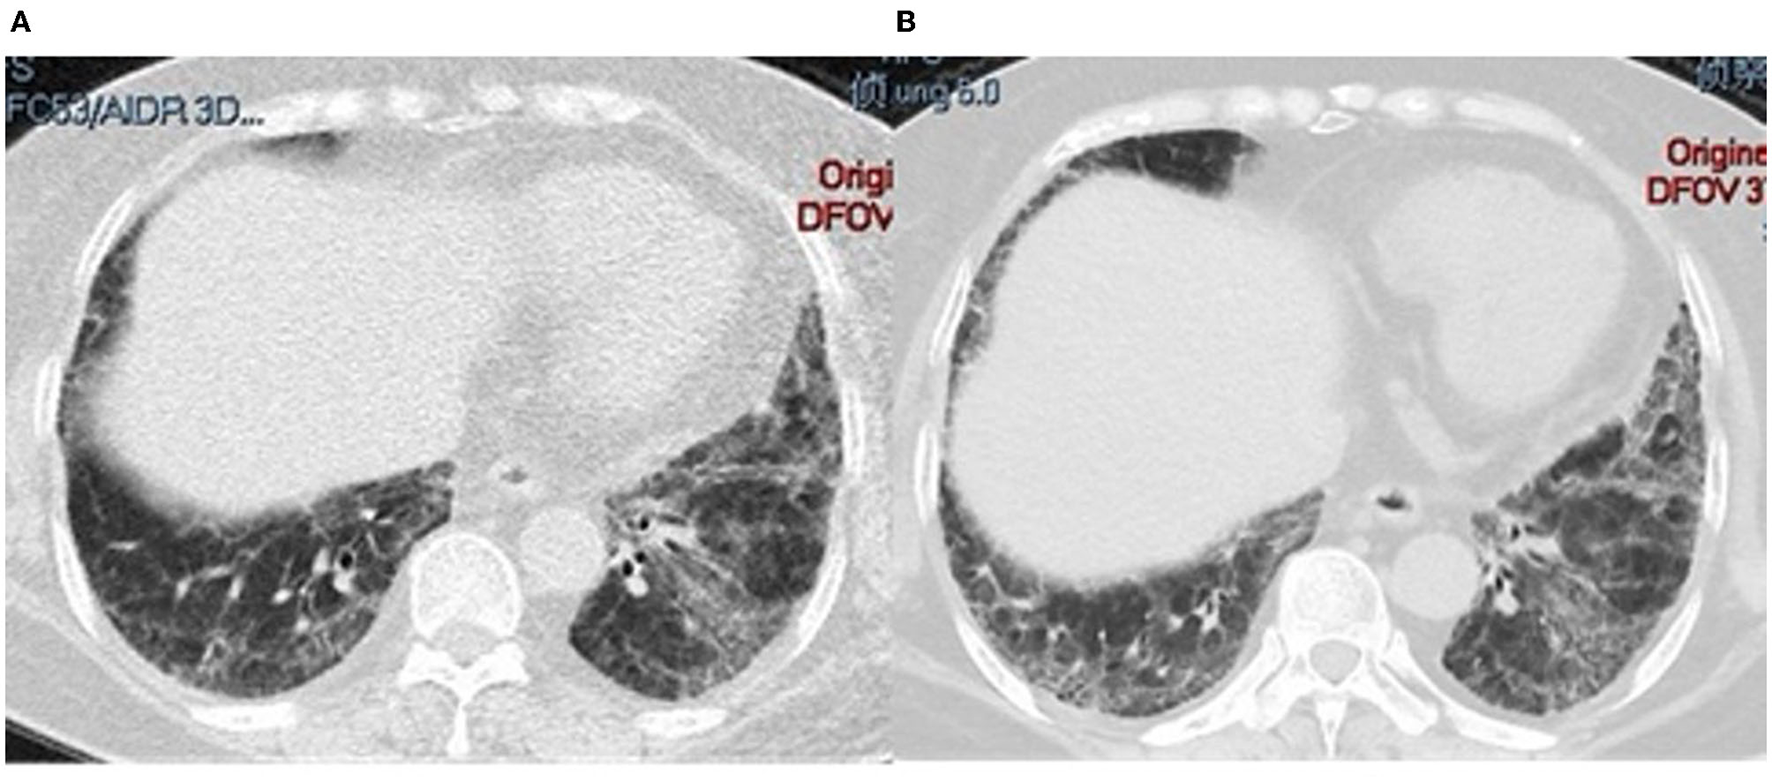

A total of 26 (86.7%) patients were diagnosed with ILD by lung HRCT; cough and/or dyspnea were the first symptoms in 15 (50%) patients. In addition, ILD was the sole manifestation in 8 (26.7%) patients. Three (10%) patients experienced mild pulmonary arterial hypertension. The pattern of ILD was evaluated by HRCT or lung biopsy: 15 (58.0%) NSIP, 5 (19.2%) patients with UIP, 4 (15.4%) with OP, NSIP with OP overlap in one patient (3.8%), and 1 (3.8%) with LIP. Representative HRCT images are shown in Figure 3.

Figure 3

HRCT from different patients who tested positive for anti-PM/Scl. (A) 41-year-old man; (B) 52-year-old man; (C) 83-year-old woman; (D) 41-year-old woman.

Lung CT changes in a 41-year-old man with PM/Scl-75 and−100. (A) CT at onset; (B) ILD progression after 8 months of treatment with an anti-fibrotic drug.